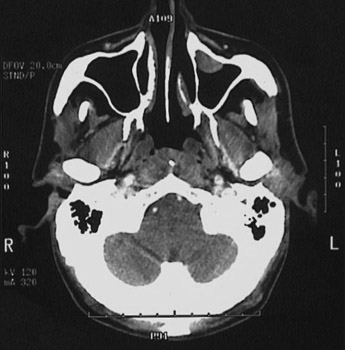

This is a normal axial head and neck CT scan demonstrating the nasal septum and nasopharynx and maxillary sinus and zygomatic arch and masseter muscle and posterior fossa of cranium and coronoid process of mandible and mandibular condyle and lateral pterygoid muscle and internal jugular vein and internal carotid artery and mastoid.